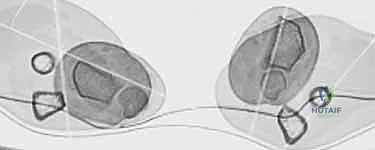

- الأشعة المقطعية (CT Scan) مع إعادة البناء ثلاثي الأبعاد (3D Reconstruction): هذه الخطوة حاسمة. تتيح للدكتور هطيف رؤية العظم من جميع الزوايا، وتحديد مكان القص بدقة متناهية.